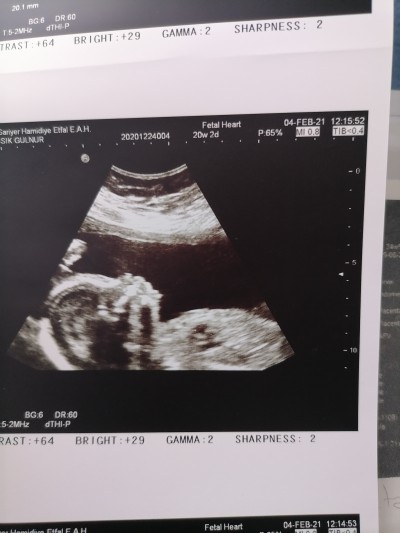

Nasil tarif ederbilirsiniz bilmiyorum ama doktor dün yüzünü vereyim dedi tamam dedim aldım.  Eve geldim tahmin yürütüyorum.  Yardımcı olurmusunuz.

Gebelik haftası 31+6

Canim ben yüz goremiyorum sanki bebegin kafasinin tepesini çekmiş yani beyin tarafı ona benzettim yüz boyle olmaz ki sağlıkla al yavrunu

On dkdir yüz arıyorum kafanın üstü gibi sanki:)

Bence kafatasğnın iç kısmı burası yüzü olsa baya belirgin olurdu

Bana kafasını yukarıdan çekmiş gibi geldi